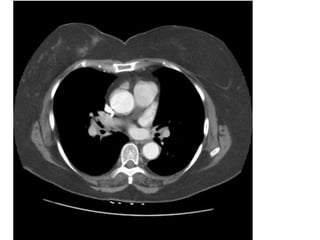

Figure 18. Tăng áp động mạch phổi thứ phát sau PE mạn ở bn nam 62 tuổi

(cùng của bn hình 12).

- Đường kính động mạch phổi 41 mm. (bình thường < 30 mm).